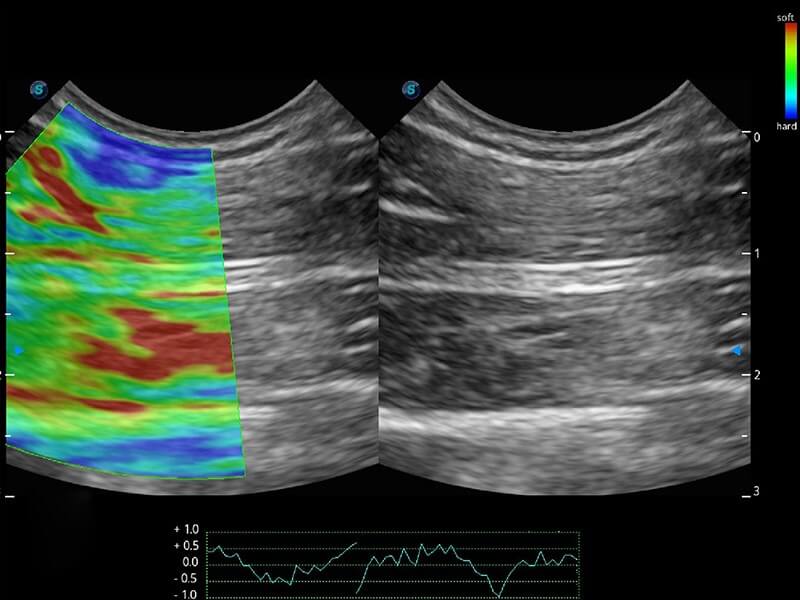

Przy pracach nad aparatem ProPet 60 uwzględniono najważniejsze preferencje i potrzeby weterynarzy, oferując finalnie przystępne cenowo i odpowiednio wyważone połączenie znakomitej precyzji klinicznej, zwiększonej wydajności i przemyślanego przebiegu pracy, niezastąpione w codziennej praktyce weterynaryjnej. Dzięki dostępowi do pełnej gamy głowic HD rozwiązanie to spełnia wszystkie potrzeby w zakresie obrazowania, umożliwiając wykonywanie badań jamy brzusznej, małych narządów, ortopedycznych, badań podczas rozrodu, a nawet badań serca i klatki piersiowej, a to wszystko przy doskonałym stosunku jakości do ceny.